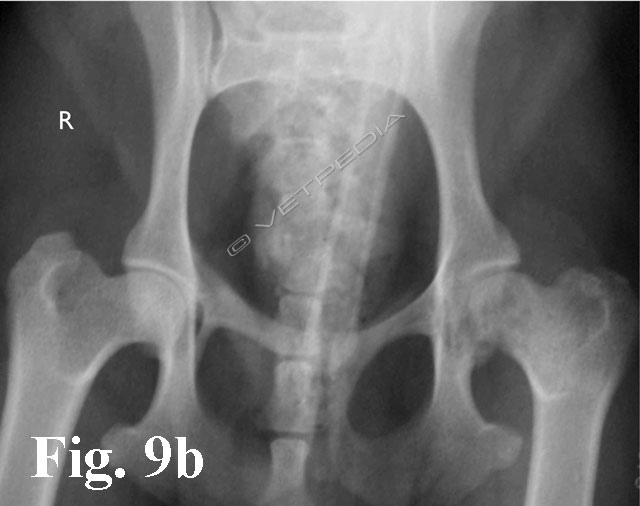

{{/_source.additionalInfo}}La necrosi asettica della testa del femore è anche denominata malattia di Legg Calvè Perthes e necrosi avascolare della testa del femore. Si tratta di un'affezione ortopedica coinvolgente l’articolazione coxofemorale di cani di razza toy o di piccola taglia durante il periodo dell’accrescimento, ad interessamento più frequentemente monola